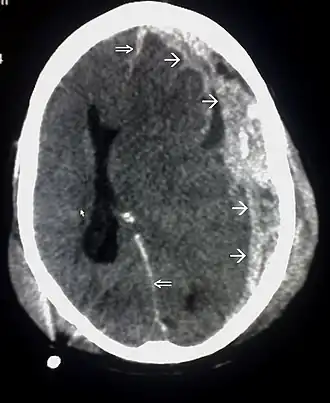

CT-scan waarop een hersenkneuzing, hersenbloeding, subduraal hematoom en schedelfracturen te zien zijn.[1]